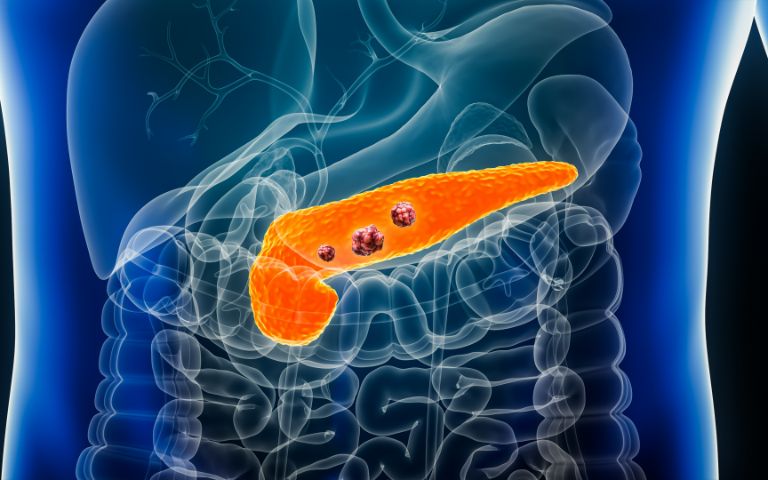

膵臓は「沈黙の臓器」と言われ、膵がんが見つかった時点では、もはや進行していることが多く、がん死亡原因の第4位となっています。たとえ、切除可能膵がんであっても、多くが遠隔転移のリスクを持っていて、膵がんの相対5年生存率は9.8%と報告され、予後不良の悪性腫瘍のひとつとされています。

これは膵がんが発見された時点で、Stage IV症例(最も悪い状態)が約半数弱を占めており、早期の段階での診断が難しいためと言われています。早期の段階では無症状かつ腫瘍マーカーの上昇も伴わないことが多いうえに、CTや腹部エコーを受けていたとしても画像に写らないこともあるからです。実際、多くの基幹病院でも早期診断された膵がん(Stage 0、Stage IA(腫瘍径10mm未満))の治療例は、非常に少ないのが現状です。私の勤務していた京都医療センターでもStage 0, Stage IAで切除された膵がんは10年間で数例しかありません。

しかし、膵がんの予後を改善するためには早期診断に努めなければなりません。先人の努力によって、Stage 0、Stage IAの診断比率は何とか20%近くまで診断できるようになってきました。早期診断して治療できると、10年生存率はStage 0で94.7%、Stage IAで93.8%と報告されています。欧米2016年の報告でも、腫瘍径が最も生存率に影響する因子であることが報告されています。つまり、小径で発見できれば膵がんの予後を改善できるのです。

膵がんの予後改善のためには腫瘍径10mm以下の早期の膵がんの発見および治療介入が重要となります。